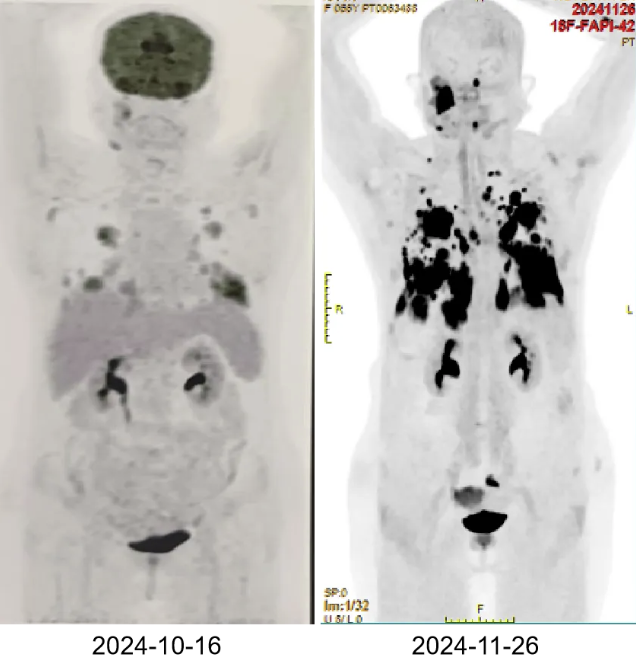

11月26日,再次行全身FAPI-PET-CT检查提示:1.右侧颞下部 FAP 高摄取肿块影,考虑为恶性肿瘤(间叶来源恶性肿瘤?恶性淋巴瘤?),建议核医学科分子影像PET/CT引导下穿刺活检(活部位见图)。2.双肺各叶多发结节、斑片及团块状实变病灶,FAPI摄取明显增高,对比外院2024-10-16PET/CT数目较前增多、范围较前增大,考虑为双肺多发转移瘤。3.双侧颈部(I、II区)、双侧肺门、纵隔内、双侧腋窝、左侧内乳区、心膈角区多发增大淋巴结。部分FAPI摄取增高,考虑为多发淋巴结转移。患者12月2日右侧颌面部活检病理结果回报:B细胞淋巴瘤,倾向弥漫大B淋巴瘤。骨穿结果:送检骨髓组织增生大致正常,三系均可见,粒红系大致正常,均以中晚幼阶段为主,巨核可见,以成熟分叶核为主,未见肿瘤。

图6:复查PET-CT提示右侧颌面部及双肺多发病灶代谢较前明显增强

图7:右侧颌面部病灶较前明显增强